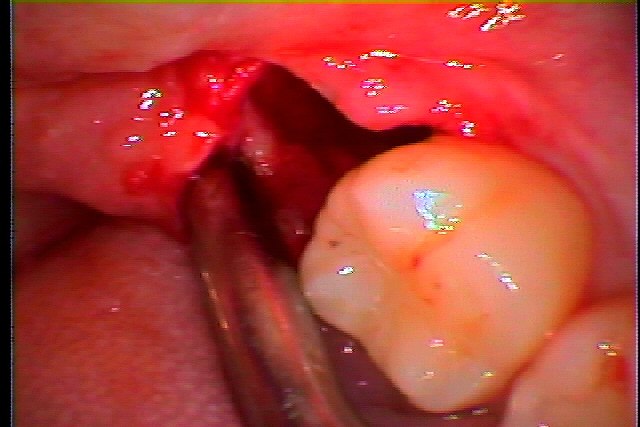

左下親知らずの完全埋伏の抜歯 時たま痛むとのこと 抜いてほしい|お知らせ |広島市安佐南区の歯科医院 左下親知らずの完全埋伏の抜歯 時たま痛むとのこと 抜いてほしい トップ お知らせ・ブログ お知らせ 左下親知らずの完全埋伏の抜歯 時たま痛むとのこと 抜いてほしい 左下親知らずの完全埋伏の抜歯 時たま痛むとのこと 抜いてほしい 少し歯茎が腫れて赤くもなっています ここに親知らずが埋まっています このように埋伏しています パノラマでしたらわかりやすいです 麻酔をかけ少し切開を加え、開いて見えるようにしていきます 抜歯した親知らずになります 分割をしています このような大穴が開きます 縫合して終了となります Web診療予約 初めての方へ 選ばれ続ける理由 院内設備について 歯が痛いしみる一般歯科 歯がぐらぐらする歯周病 健康な歯を保ちたい予防歯科 子供の虫歯予防をしたい小児歯科 銀歯をセラミックに審美歯科 白い歯を目指しませんか?ホワイトニング 矯正専門医がいるので安心矯正歯科 抜けた歯を補いたいインプラント・入れ歯 医院案内 スタッフ紹介 メリィハウス歯科クリニックオフィシャルホームページ ラベンダー歯科クリニックオフィシャルホームページ お知らせ・ブログ ホーム 診療科目 一般歯科 歯周病治療 予防治療 小児歯科 審美治療 ホワイトニング 矯正歯科 入れ歯・インプラント マウスピース矯正 初めての方へ 院長・スタッフ 設備紹介 医院案内・アクセス メニューを閉じる